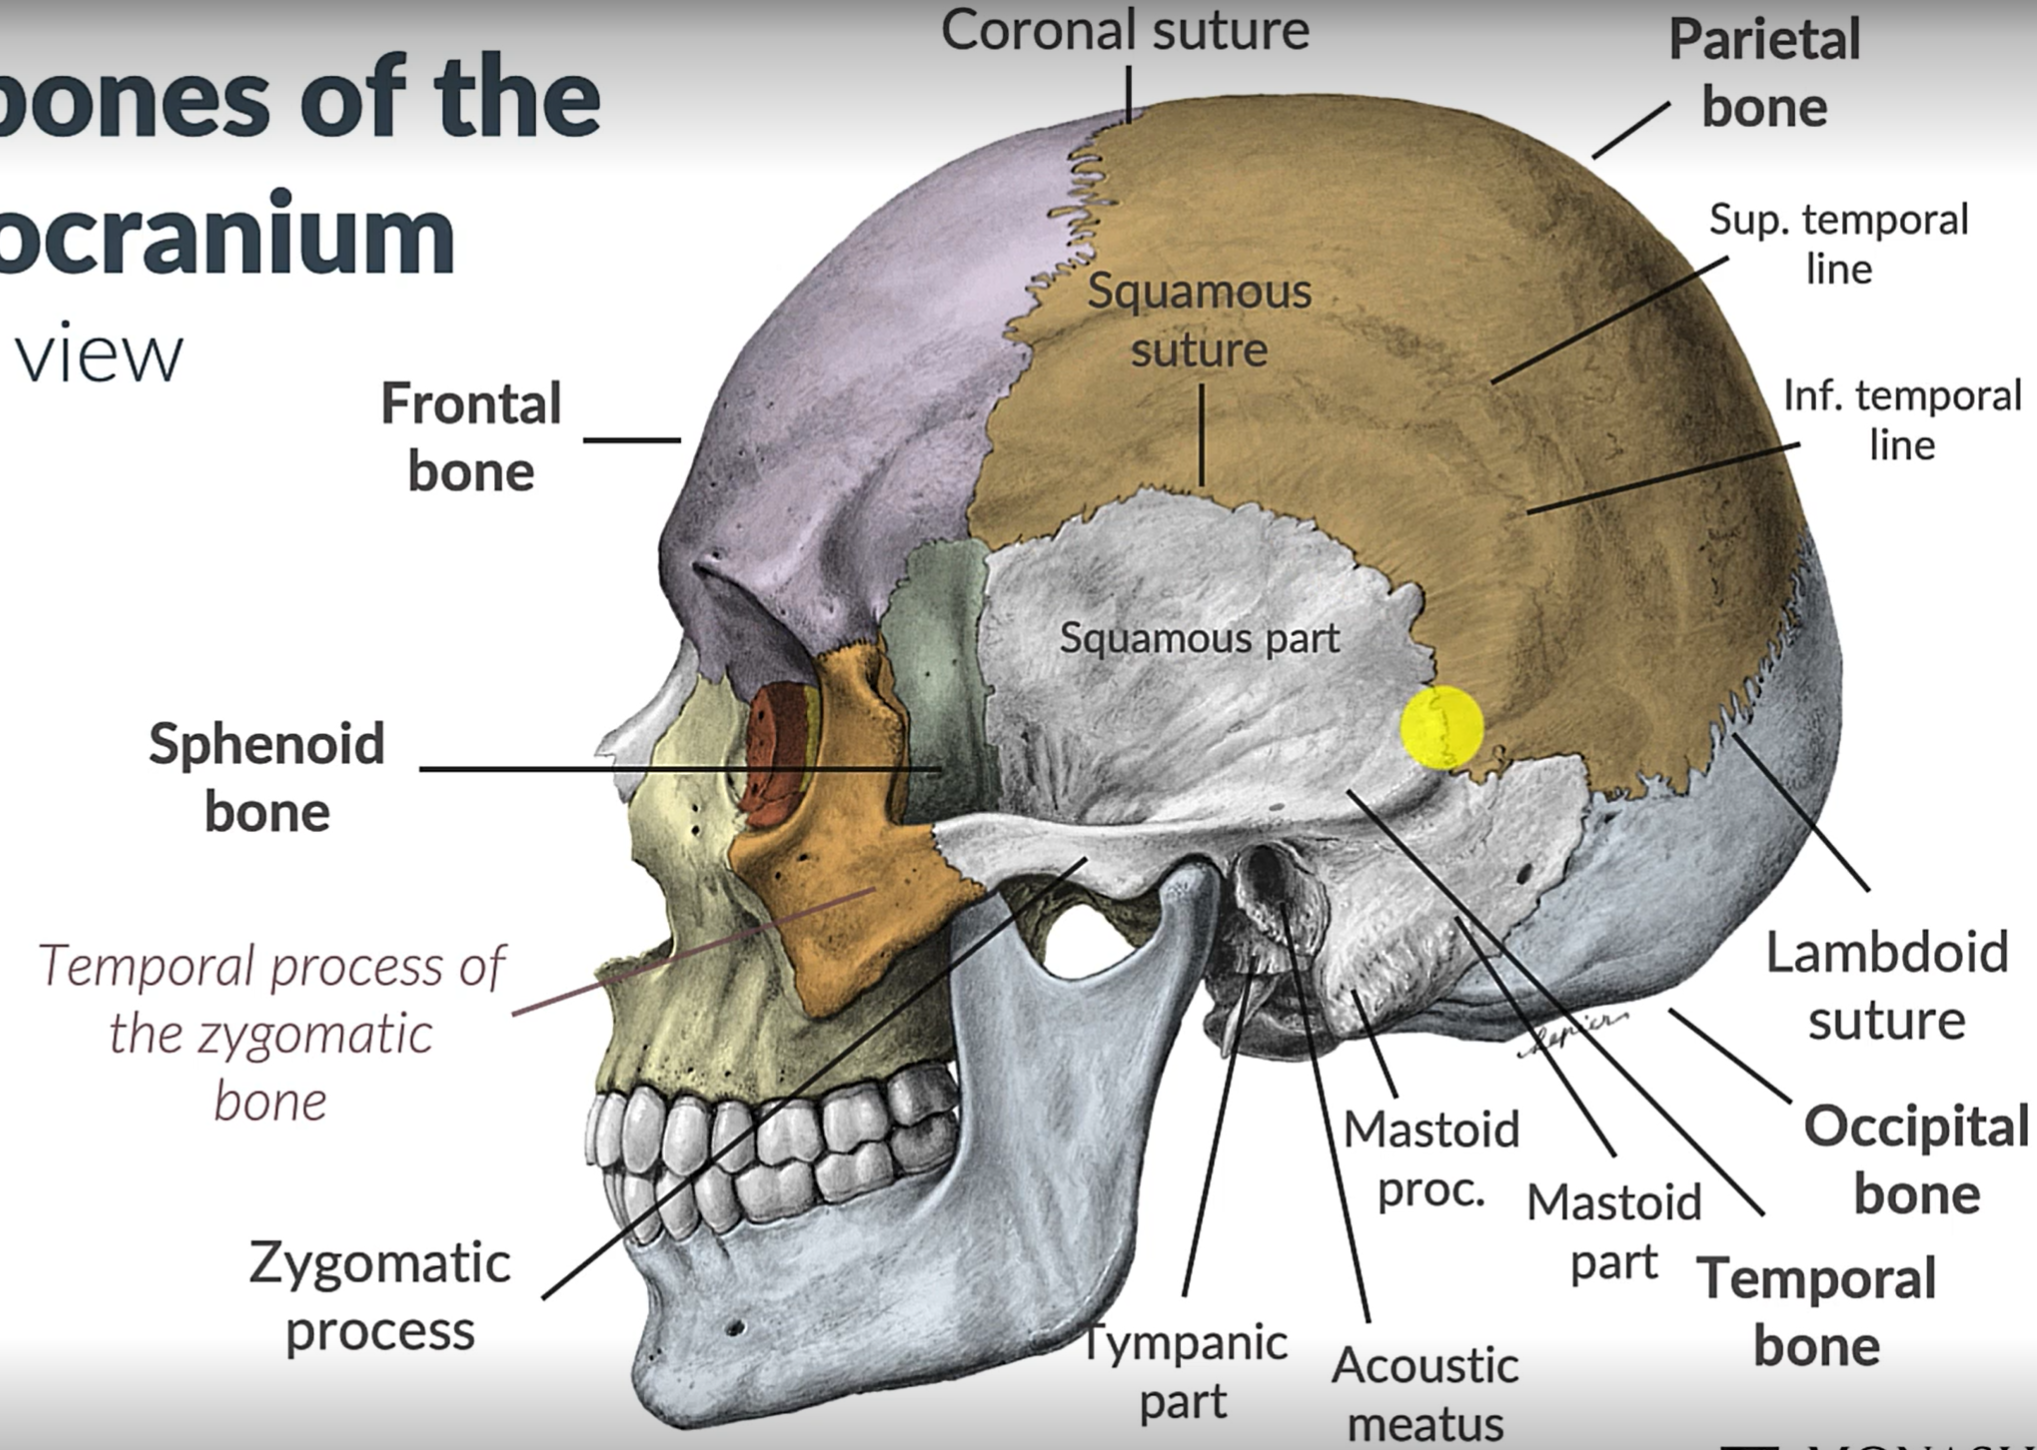

Parietal bone

Frontal bone

Temporal bone

Sphenoid bone

Zygomatic bone

Coronal suture

Squamous suture

Lambdoid suture

Occipital bone

Temporal bone

Zygomatic process

Sphenoid bone